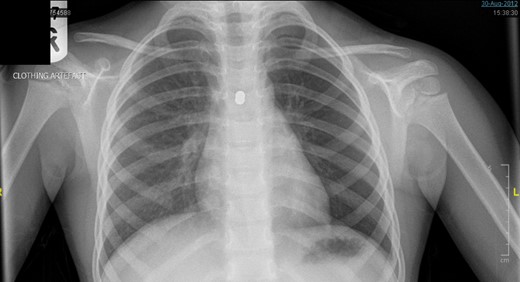

A 3-year-old girl was referred to the asthma clinic with a 3-month history of morning cough and wheeze. She was seen multiple times by her general practitioner (GP) who initially diagnosed her with upper respiratory tract infection. Her symptoms persisted despite salbutamol inhaler treatment so the GP organised a chest x-ray (CXR) (Fig. 1). It was reported that the left lung was translucent with reduced peripheral lung markings: finding consistent with asthma with bronchial plugging or a post infective bronchiolitis. It also showed a round radio-opaque FB over the left main bronchus. However, this was labelled as ‘Clothing Artefact’ on the actual radiograph and therefore did not alarm the GP or the reporting radiologist. A repeated PA CXR (Fig. 2) was undertaken in the asthma clinic where all clothes and hair were removed from the thorax. This confirmed the presence of a metallic FB in the left main bronchus and the patient was immediately admitted for bronchoscopy and removal of the FB.

The repeated posterior–anterior CXR taken with all clothes and hair removed from the thorax of the patient. It confirmed the presence of a metallic foreign body in the left main bronchus.